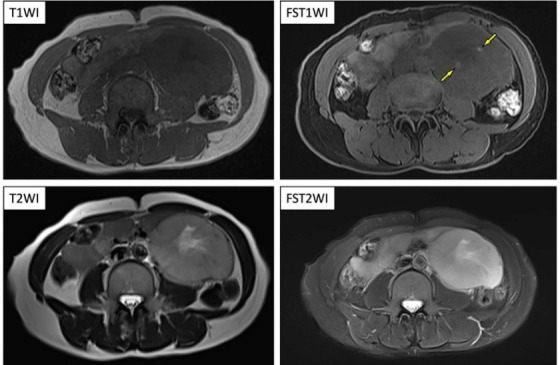

一名 50 岁的妇女经全身体检被诊断为缺铁性贫血。对比增强腹部 CT 和磁共振成像显示,腹膜后间隙有一个巨大的高血管肿块,内部变性坏死。她被转到我院接受进一步评估和治疗。由于副神经节瘤是最有可能的影像学诊断,因此对她进行了 123I-MIBG 闪烁扫描。结果显示,腹膜后病变处有明显的异常积聚,提示为副神经节瘤,未发现其他异常积聚。血浆中的几种儿茶酚胺及其尿液代谢物均正常。在随后的 18F-FDG PET/CT 检查中,发现腹膜后病灶有较高的 FDG 摄取(SUVmax=38)。右肺下叶底部的一个小结节也发现了 FDG 摄取(SUVmax= 9.8)。对比增强成像显示右肺底部有一个高血管结节,提示副神经节瘤肺转移。切除了腹部病灶和右肺结节,根据病理结果诊断为腹膜后副神经节瘤和肺转移。在该病例中,18F-FDG PET/CT 在寻找副神经节瘤转移灶方面发挥了作用。我们报告了 123I-MIBG 在副神经节瘤中的蓄积与 18F-FDG 摄取之间的关系,并回顾了相关文献。

A 50-year-old woman was diagnosed with iron deficiency anemia on general medical examination. Further, contrast-enhanced abdominal CT and magnetic resonance imaging revealed a large hypervascular mass with internal degeneration and necrosis in the retroperitoneal space. She was referred to our hospital for further evaluation and treatment. Because the paraganglioma was most likely as the imaging diagnosis, 123I-MIBG scintigraphy was performed. It revealed the marked abnormal accumulation in the retroperitoneal lesion indicating the paraganglioma and no other abnormal accumulation was noted. Several plasma catecholamines and their urinary metabolites were normal. On the subsequent 18F-FDG PET/CT, high FDG uptake was found in the retroperitoneal lesion (SUVmax=38). FDG uptake was also found in a small nodule at the base of the lower lobe of the right lung (SUVmax= 9.8). Contrast-enhanced imaging revealed a hypervascular nodule at the base of the right lung, suggesting pulmonary metastasis of a paraganglioma. The abdominal lesion and right lung nodule were excised, and retroperitoneal paraganglioma and pulmonary metastasis were diagnosed based on the pathology findings. In this case, 18F-FDG PET/CT was useful in the search for paraganglioma metastasis. We report a relationship between 123I-MIBG accumulation and 18F-FDG uptake in paraganglioma and review the relevant literature.